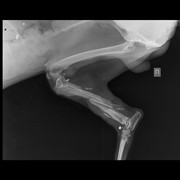

Еще одна свежая история спасения собаки из Сосновки. В субботу, 14 марта, мне позвонили из Сосновки, и сказали, что около магазина лежит собака, у которого болтается лапа и торчит кость.

В понедельник Пал Палыч, известный доктор из Лиды, сделав рентген и взяв анализы, ужаснулся, как пес остался жив. В него стреляли как в мишень. Дробь во всем теле. А лапу перебили палкой, либо каким то тяжёлым предметом.

Сейчас Барни, так назвал его Денис,, на лечении чтобы снять воспалительный процесс и нормализовать анализы. Готовят мальчика к операции. Что будет с лапой, удастся ли ее спасти, пока неизвестно.

Денис будет писать заявление в РОВД по поводу расстрела собаки. Охотников в Сосновке нет. Модет иметь место не зарегистриванное орудие или пнематика.